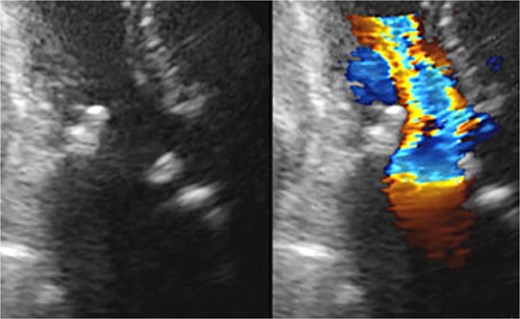

A 70-year-old woman (body surface area [BSA] 1.42 m2) had undergone aortic valve replacement (St. Jude Medical 19 mm mechanical aortic valve; Abbott, St. Paul, MN, USA), mitral valve repair (Physio Ring 24 mm; Edwards Lifesciences, Irvine, CA, USA), and tricuspid annuloplasty with De Vega technique 13 years earlier. Over the previous two years, she experienced progressive heart failure despite optimized medical therapy. Echocardiography demonstrated severe mitral stenosis with a mitral valve area of 0.96 cm2, markedly restricted leaflets, and calcification of both commissures. The aortic prosthesis showed a peak velocity of 3.3 m/s with moderate stenosis and moderate paravalvular regurgitation (Fig. 1). Given persistent symptoms and limited efficacy of medical management, surgical intervention was planned. Her comorbidities included hypertension and chronic atrial fibrillation.

Preoperative transthoracic echocardiography: significant paraventricular leakage was shown with the white arrow.